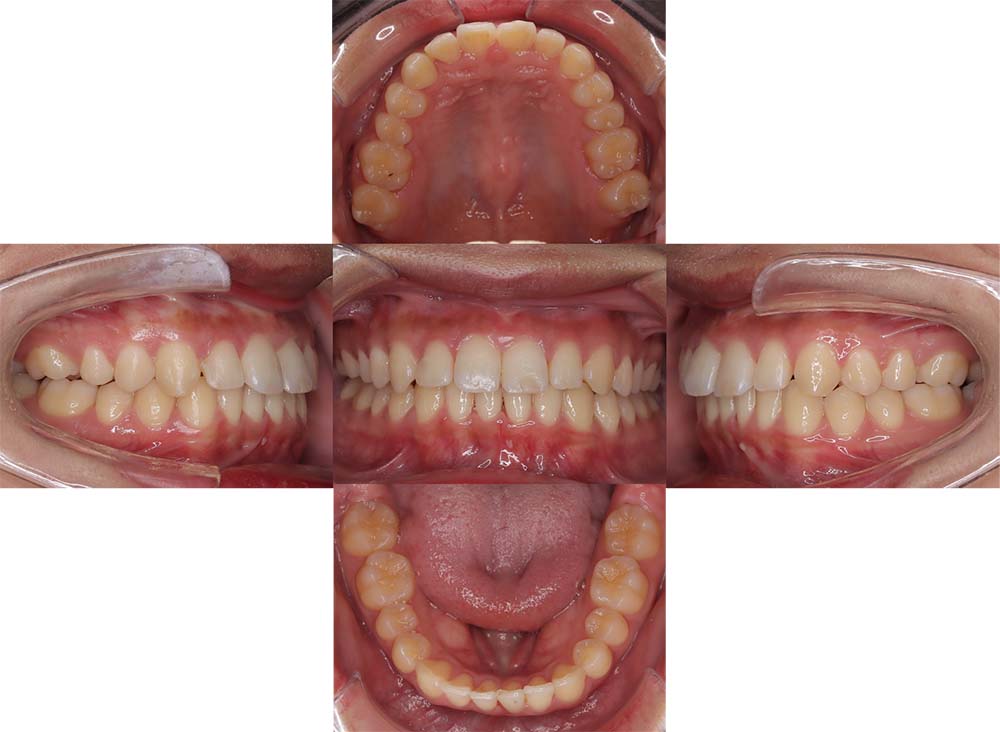

症例02

| 主訴 | 下あご顎が出ている。曲がっている。 |

| 診断名あるいは主な症状 | 反対咬合、非対称、空隙歯列、過蓋咬合 |

| 年齢/性別 | 19歳・女性 |

| 矯正ステージ | 大人の矯正治療 |

| 治療方法 | ワイヤー矯正、顎矯正手術の施行 |

| 抜歯部位/抜歯有無 | 非抜歯 |

| 治療内容 | 上下顎歯列を並べた後に顎矯正手術の施行。 |

| 費用 | 保険治療 |

| 治療期間 | 3年2ヶ月 |

| 主なリスク・副作用 | 痛み、歯根吸収、歯肉退縮、虫歯、後戻り |